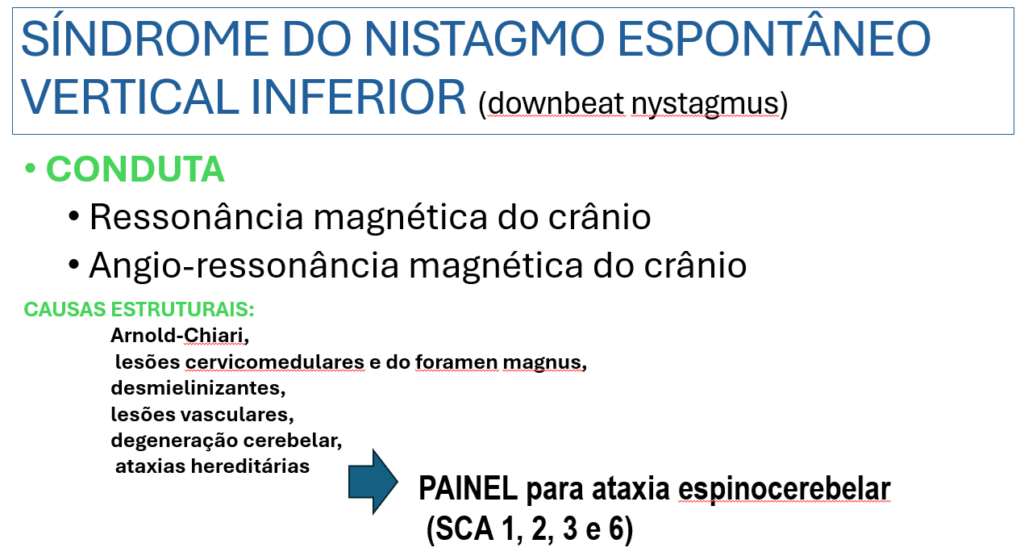

Com relação a causa do NEVI, nesse trabalho abaixo, combinaram três séries de pacientes com NEVI. Observem que há uma alta proporção de causa idiopática. Porém, cerca de 40% dos pacientes apresentaram uma explicação estrutural evidente, indicando a importância dos exames de neuroimagem.

Nesse mesmo artigo, é proposto uma classificação do NEVI em dois grandes grupos. O causado por uma patologia estrutural evidente e os de causa não estrutural.

Nesse caso, os exames de imagem não ajudaram na identificação do fator causal.

Com o objetivo de procurar um fator etiológico solicitei:

– Painel genético para ataxia espinocerebelar, dosagem de vitamina b12, b6, b1, magnésio, vitamina E, Anti Gad, ca 15.3, 19.9, 125, CEA, desidrogenase lática total, creatinoquinase total, complemento c3, c4, FAN, Anca (Anti citoplasma de neutrófilo c,p) e teste sorológico para borreliose.